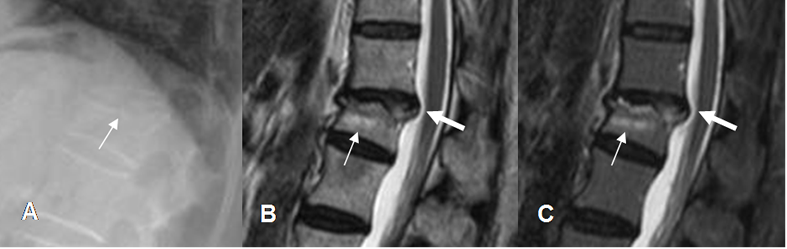

Fig 209. Hernia post-trauma.

A: Rx lateral. Pérdida de altura en la placa terminal superior de la vértebra.

B: RM sagital en T2 y C: RM sagital en STIR. Placa superior hiperintensa, por fractura de evolución aguda. (Flechas delgadas). Se aprecia hernia mediana, que indenta el saco dural. (Flechas gruesas).